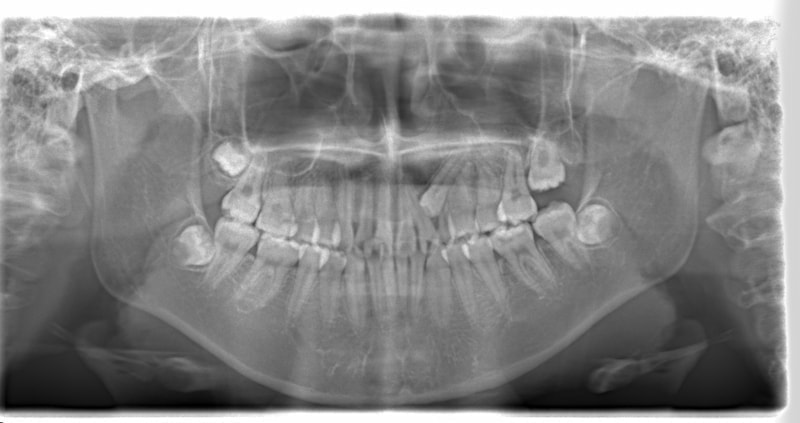

左上3番埋伏歯

治療法:フルパッシブブラケット:T21

治療前